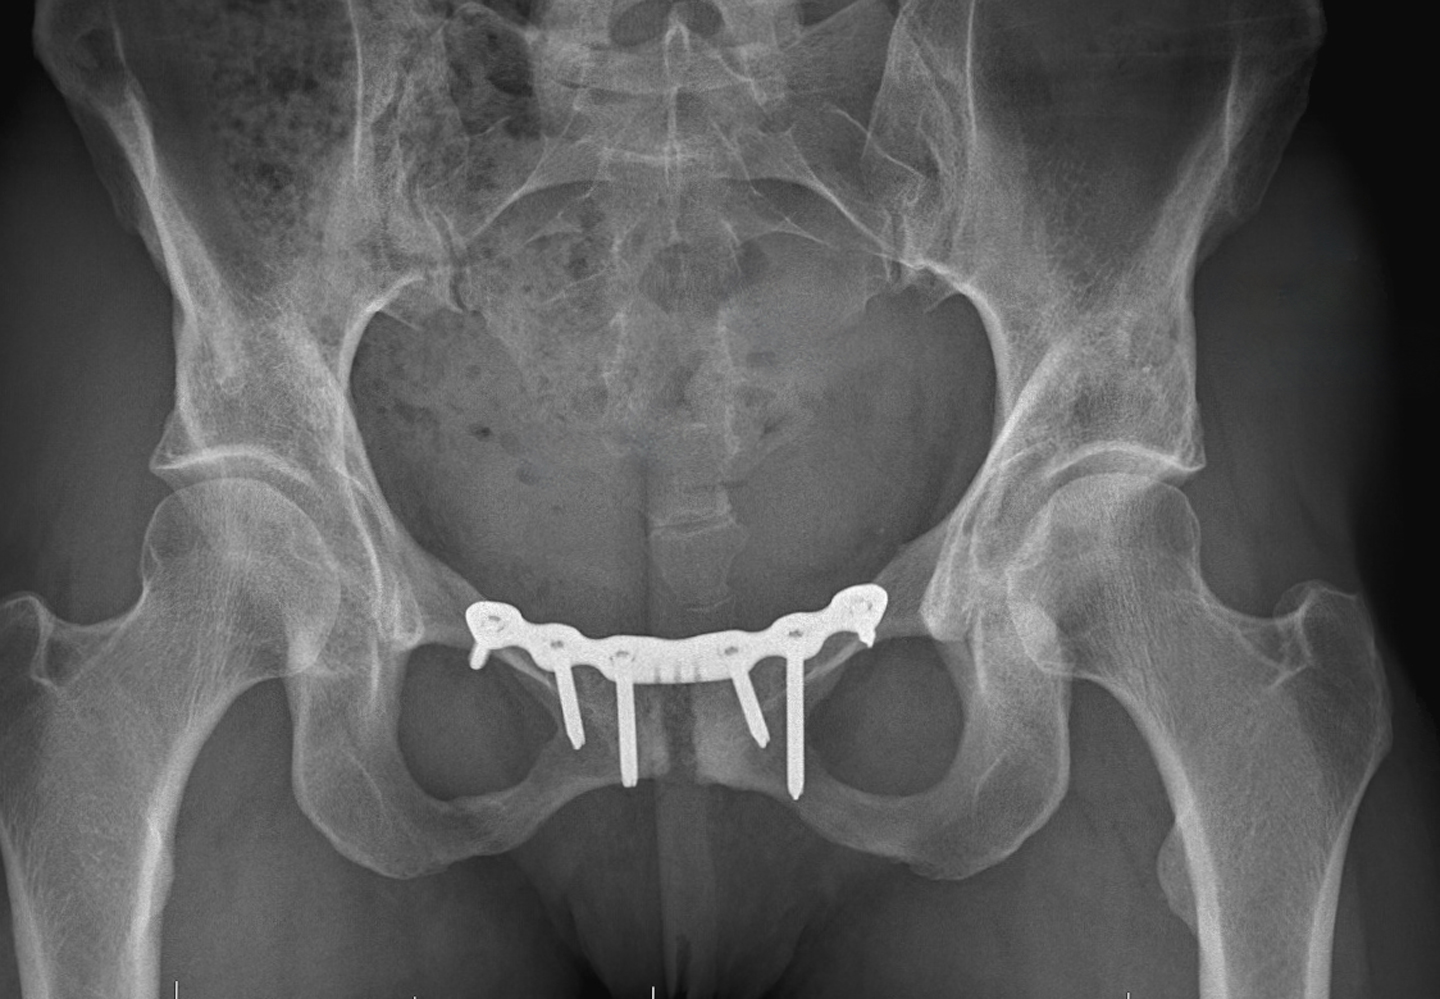

Osteitis pubis. Pelvic radiograph in a 21yearold soccer player Sports Hernia Osteitis Pubis Web osteitis pubis is most often a sports injury caused by the overuse of the hip and leg muscles. Web although many different sports may be associated with osteitis pubis, sports with a higher risk include soccer, football, ice. Web osteitis pubis : Web osteitis pubis is as an inflammatory condition of the pubic symphysis and surrounding structures. Web in. Sports Hernia Osteitis Pubis.